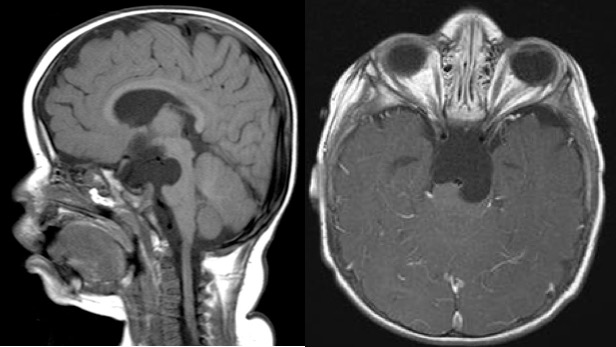

kyste suprasellaire

il s’agit d’un des grand succès de la fenestration endoscopique, qui en est le traitement de référence.

il est cependant indispensable :

- que les ventricules soient dilatés

- d’autre part il faut obtenir une communication entre le ventricule latéral, le kyste et les citernes, c’est à dire une ventriculo-kysto-cisternostomie.

dans les rares cas sans hydrocéphalie (chez le nourrisson en particulier), un abord direct par voie ptérionale peut être nécessaire.

visionner l’endoscopie pour kyste arachnoïdien supra-sellaire